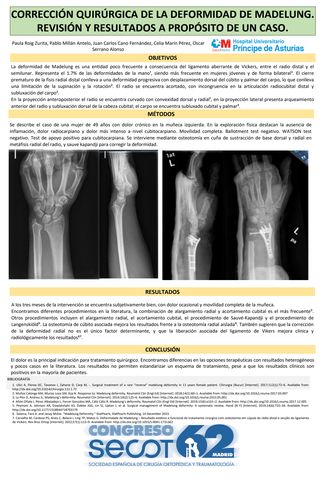

CORRECCIÓN QUIRÚRGICA DE LA DEFORMIDAD DE MADELUNG. REVISIÓN Y RESULTADOS A PROPÓSITO DE UN CASO.

PAULA ROIG ZURITA, PABLO MILLÁN ANTELO, JUAN CARLOS CANO FERNÁNDEZ, CELIA MARÍN PÉREZ, ÓSCAR SERRANO ALONSO